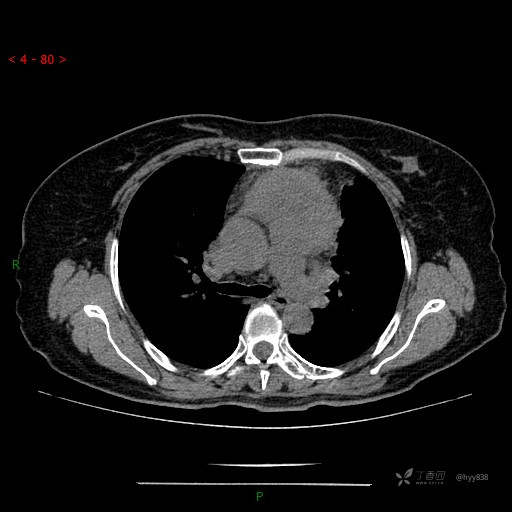

简要病史:患者诉3月余前患新冠肺炎,出现持续性胸闷,活动后可缓解,无胸前区压榨感,无畏寒发热不适,无胸痛咯血、呼吸困难,无恶心、呕吐,无腹痛、腹胀、腹泻等不适,未予以重视,未行特殊处理。患者胸闷持续存在,为进一步诊治,3天前于本院查胸部CT提示前纵膈团块状软组织密度影,肿瘤性病变可能,心包积液,左上肺磨玻璃结节,右下肺增殖灶可能建议进一步检查。门诊以“前纵膈占位” 收入我科。 患者本次起病来精神、食欲、睡眠尚可,大小便正常,体力、体重无明显变化。

辅助检查:CT

临床诊断:纵隔占位

胸部CT平扫